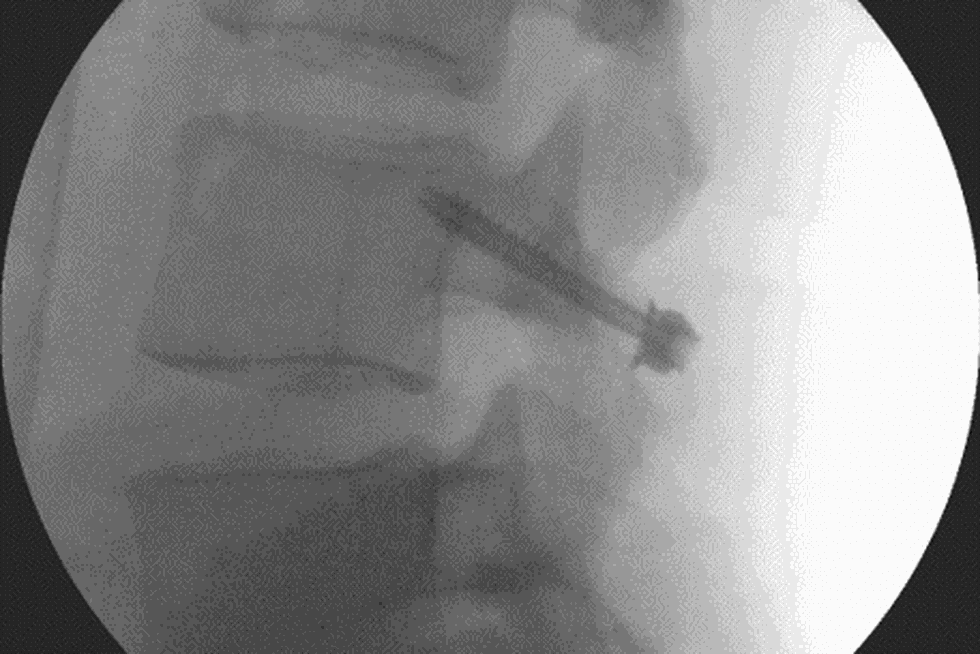

The aim of the surgery is to restore normality. It's a keyhole procedure, conducted under real-time x-ray which ensures Wilson aligns the screw just right and does not damage muscle mass. The prognosis is good. Wilson has never had what he calls a "late failure": someone breaking down again at the same vertebrae that he has fixed.

"The scan shows us that there is now complete continuity in the bone," Wilson says when he describes the x-ray on the screen in his office. "The shadow of the gap is mostly filling in and the screw looks intact, not loose, right up against the bone." Topley's scan was consistent with other successful surgeries Wilson has done.